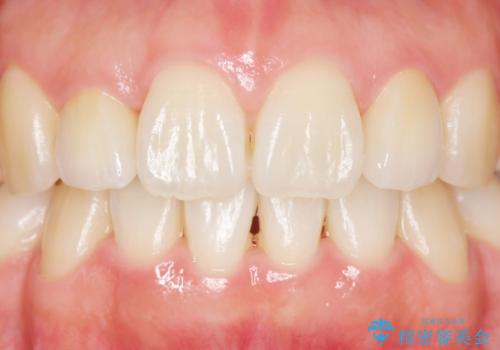

矯正治療後、矮小歯をセラミッククラウンにより理想的な歯の大きさに仕上げました。

自然な仕上がりにご満足頂けました。

「自分でもどこを治したのかわからないくらい自然!」と喜んで下さいました。

クラウンの種類:オールセラミッククラウン スペシャル